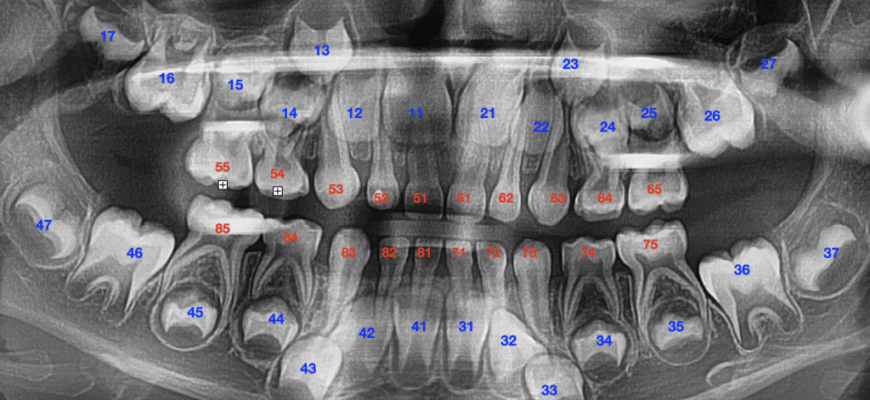

Що таке зуби мудрості?

- Восьмі моляри. Так, ті самі. В народі — зуби мудрості.

- Локація. Розташовані в задній частині ротової порожнини.

- Час появи. Іноді взагалі не з’являються. Або з’являються, коли вже не треба.

То в чому їх прикол? Відповім коротко: часто просто нема їм місця.

Чи всі мають зуби мудрості?

Існує поширена плутанина: чи потрібно взагалі мати ці зуби? Уявіть: не у всіх є зуби мудрості. А якщо є, це ще не означає, що вони компенсація чи знак великого мудрості. Деякі народи взагалі їх не мають! Чому ж так? Можливо, еволюція відбирає те, що не потрібне.

Коли зуби мудрості стають проблемою?

- Неправильне розташування. Якщо зуб прорізається під невірним кутом.

- Незручність. Краще один раз видалити, ніж вічно жувати з дискомфортом.

- Інфекція. Зуби можуть бути причиною запалень і болю. І це зовсім неприємно.

- Пошкодження сусідніх зубів. Вони не лишають шансу для сусідів. Стиснутися — єдиний вихід.

- Проблеми з яснами. Якщо з’являється карман навколо зуба — погана ознака.